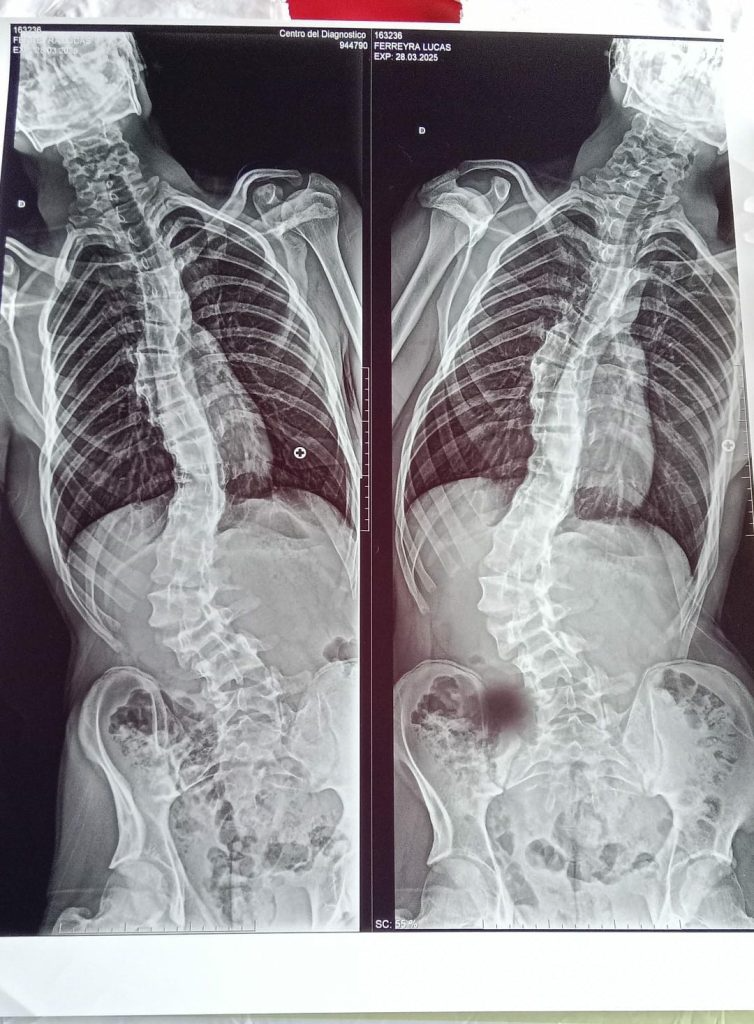

“En el 2016 le encuentran una escoliosis, tiene todos los estudios, todo este tratamiento y a los 14 años llegamos a una cirugía”, explicó la madre. Sin embargo, al iniciar el trámite para conseguir la prótesis necesaria, comenzaron los problemas: “Hicimos el pedido, el doctor me lo pide todo, llevamos los papeles a Incluir Salud, y todas las veces que viajamos a Mendoza no nos daban respuesta. Al final pudimos contactar que nos habían perdido el pedido de los 14 años de la prótesis”.

Mientras tanto, el tiempo pasa y la salud de Sebastián empeora. “Estamos viendo todos los meses con el doctor Morales, que lo va a operar. Él me dice: ‘mamá, hay que hacer ruido, porque tu hijo tiene la médula dilatada, se ha empezado a empeorar’. Era una sola operación, y ahora ya se sumaron tres operaciones, por lo que se ha seguido desviando”, relató la mujer, quien aclaró que el cirujano ya cuenta con todos los estudios previos y el quirófano asignado: solo falta el material.